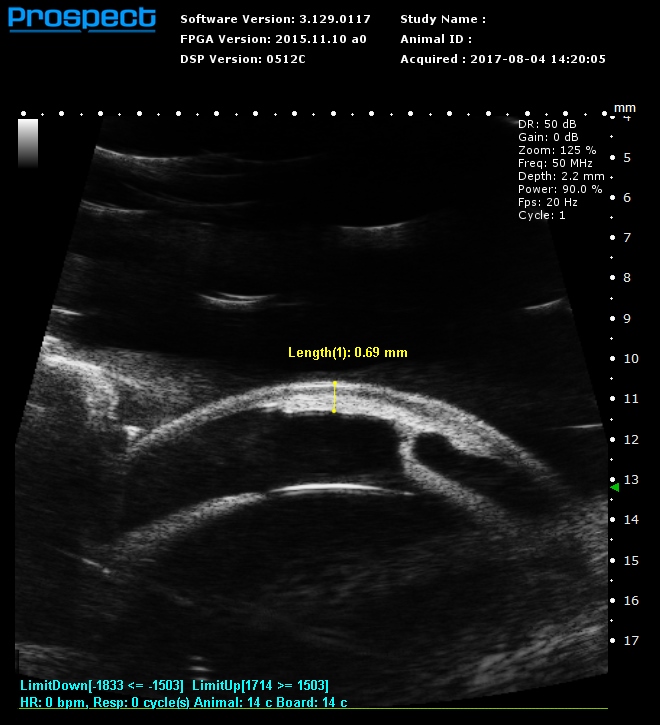

Intra-injection under 2mm mouse skin |

| Mouse eye CT imaging |